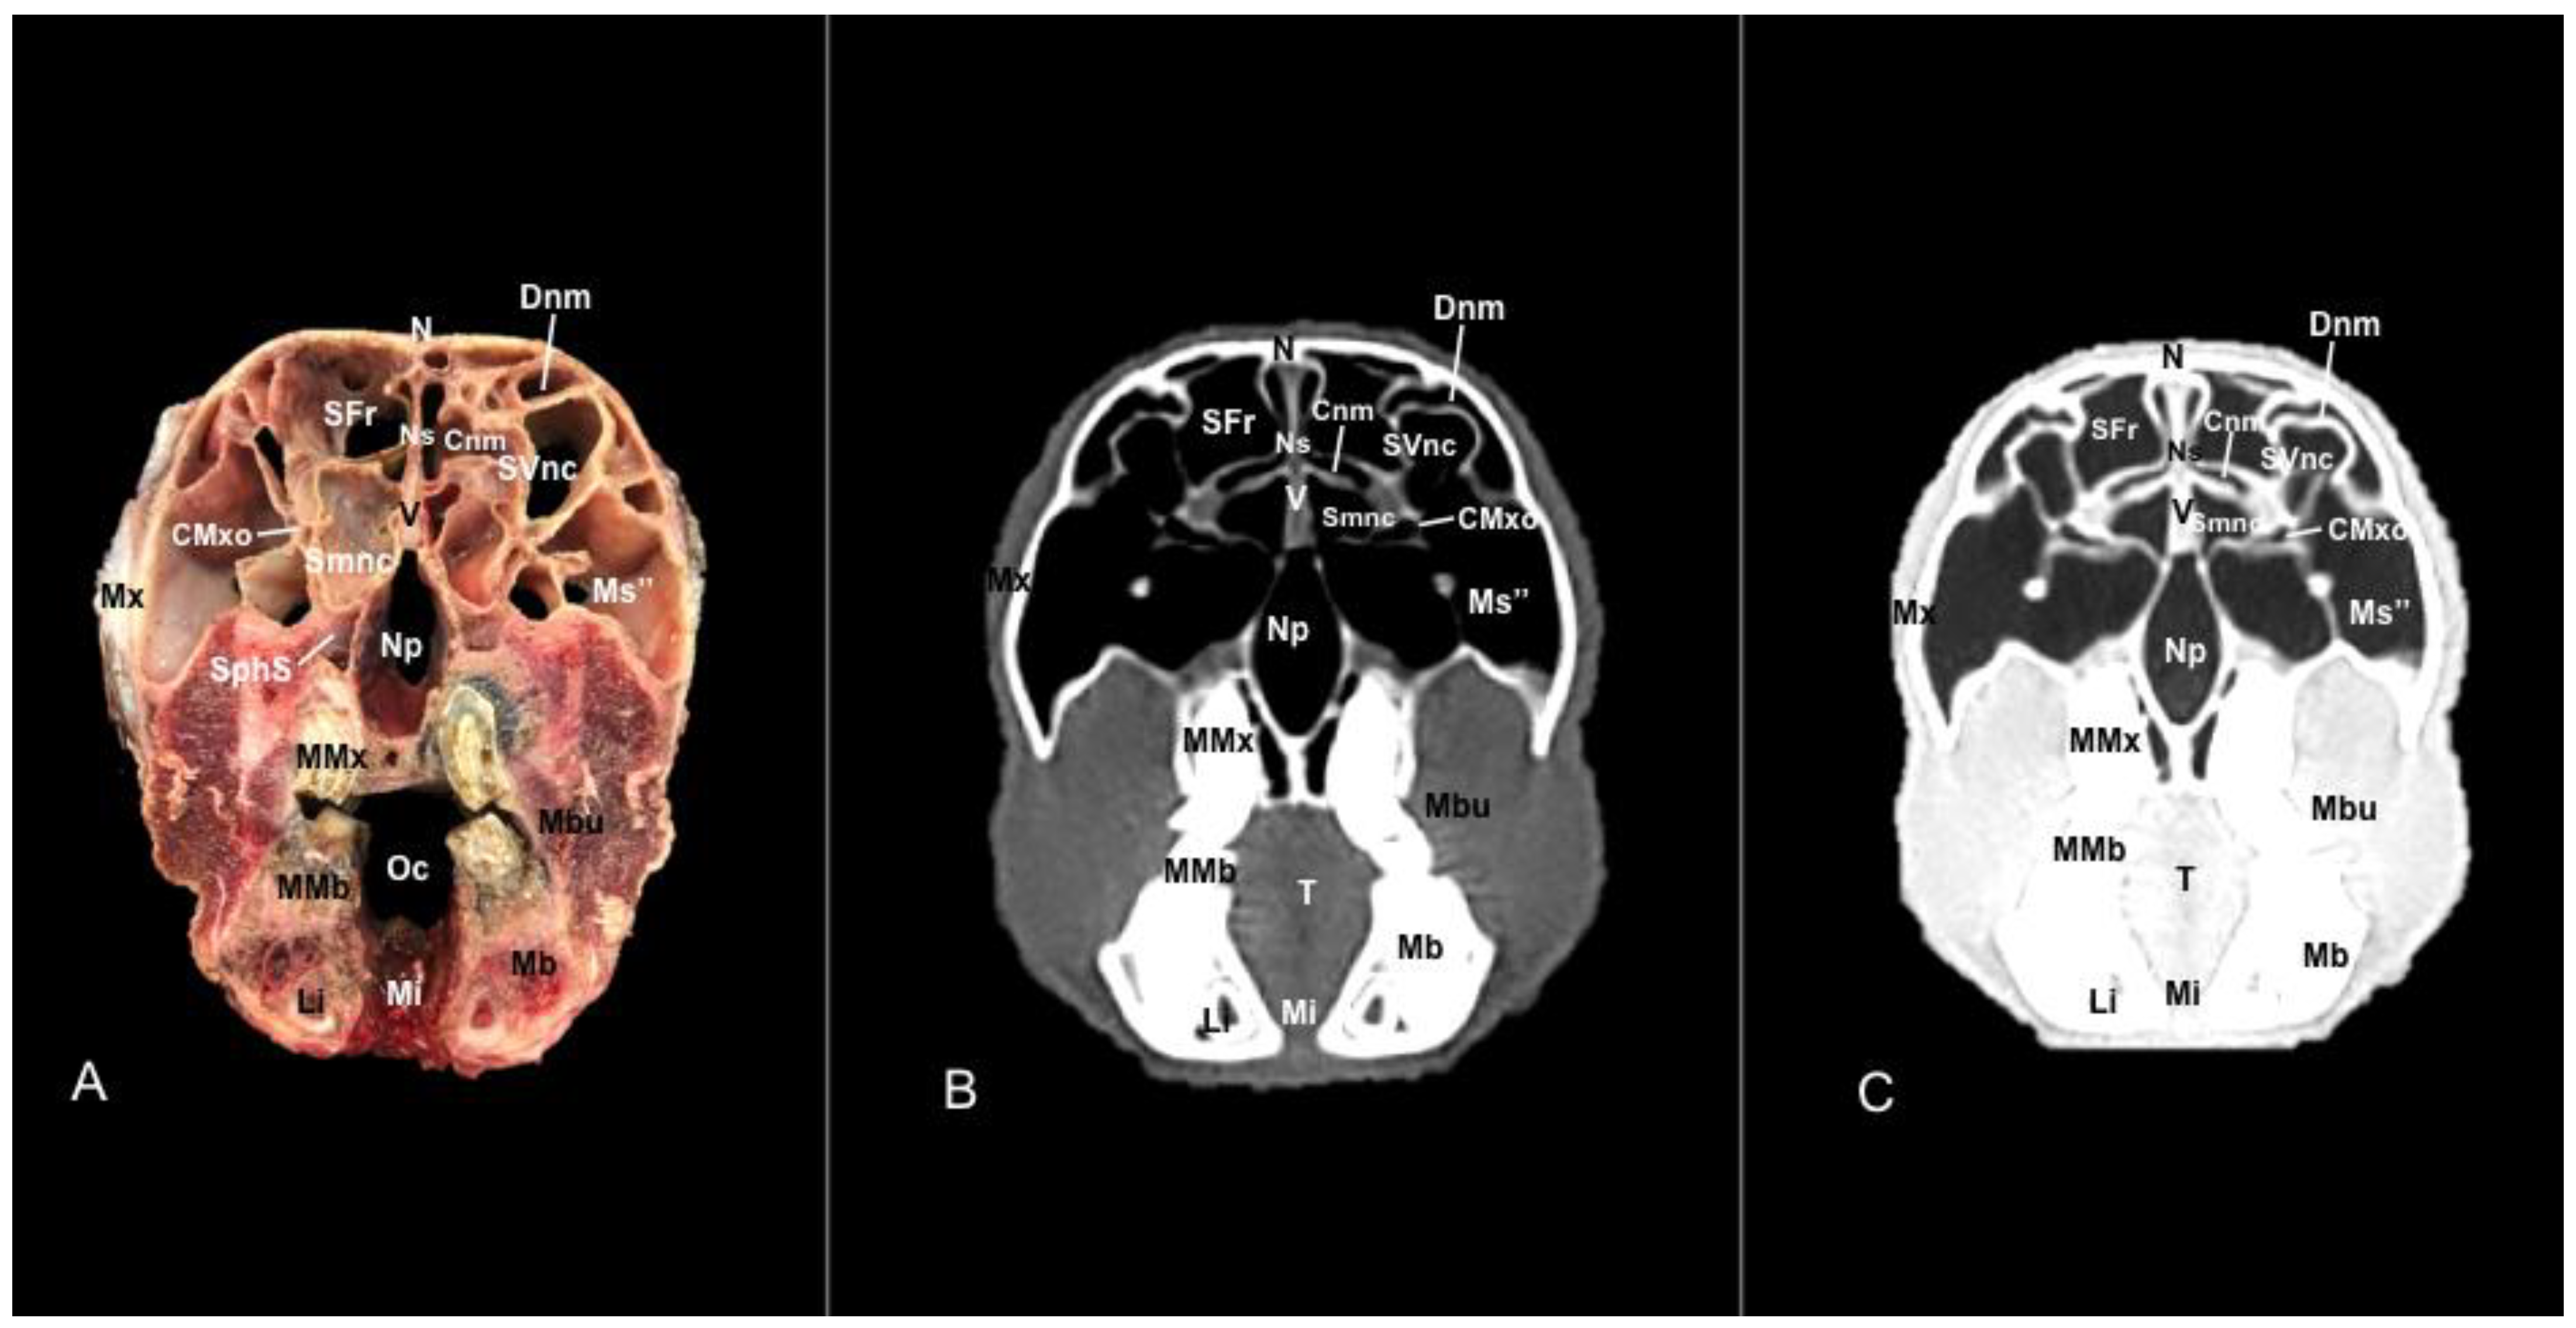

3.1. Anatomical Sections

3.2. Computed Tomography (CT)